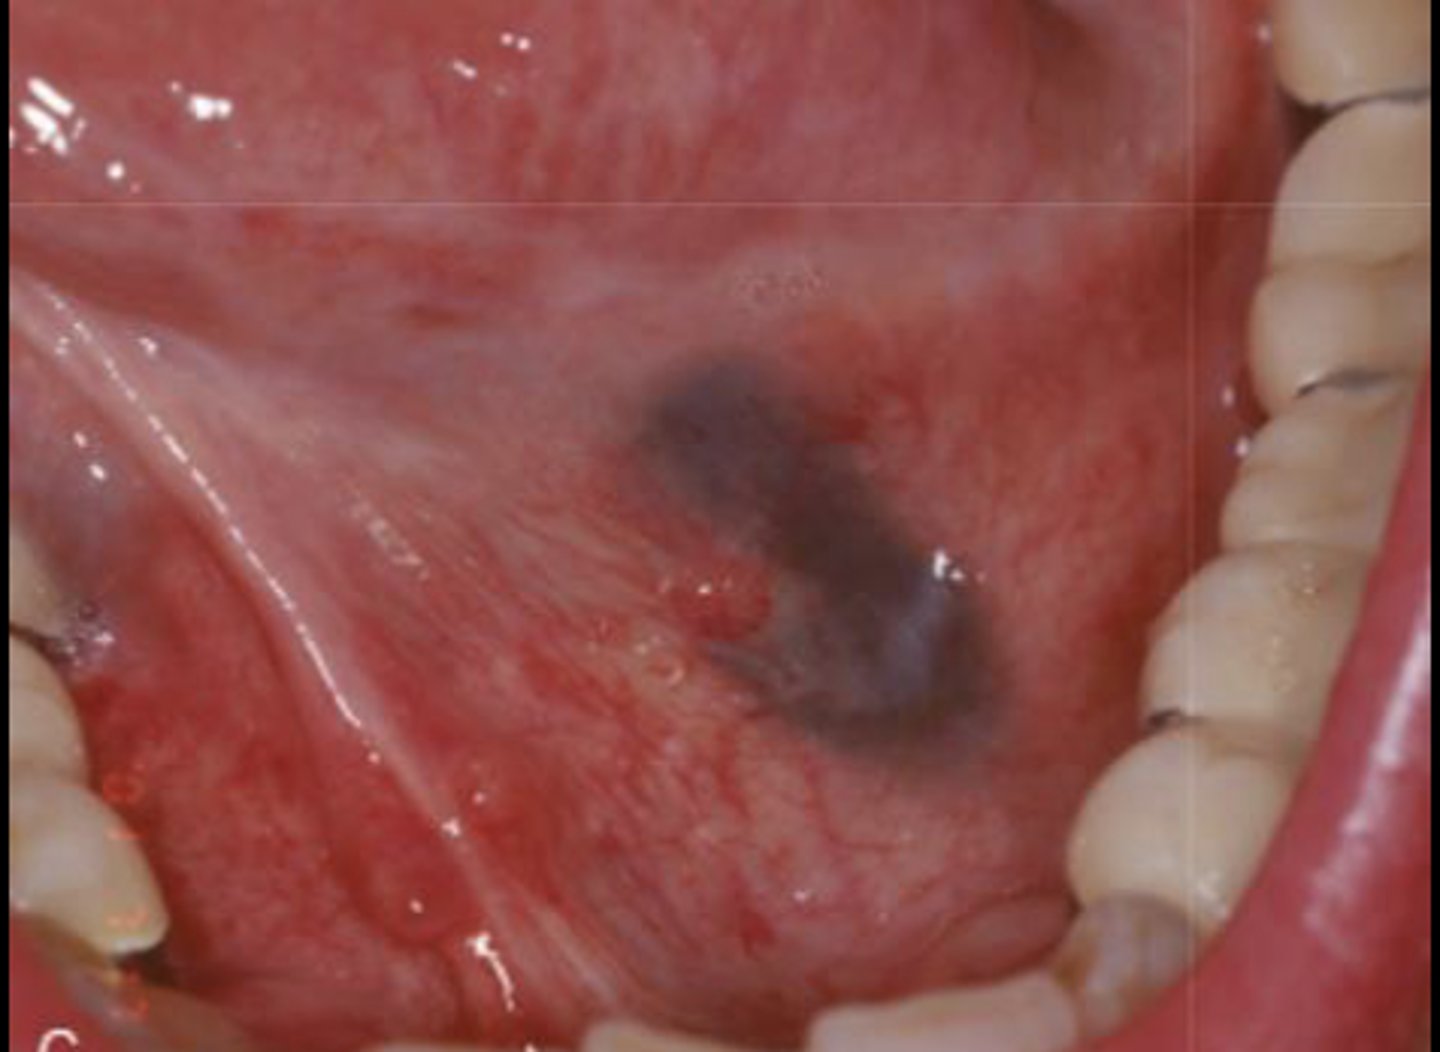

What type of pigmented lesion?

amalgam tattoo

These are clinical features of what?

- Asymptomatic, localized

- Blue-gray macule

- Localized around areas with amalgam restorations

amalgam tattoos

What is the most common location of amalgam tattoos?

gingiva/alveolar ridge mucosa (50%, then buccal mucosa, then floor of mouth)